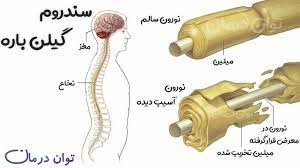

قیمت: 22٬000 تومان - دسته بندی فایل: پاورپوینتپاورپوینت سندرم گیلن باره

فروش ویژه پاورپوینت حرفه ای سندرم گیلن باره باتخفیف استثنایی فقط48000هزارتومان تعداداسلاید.14اسلایدکامل